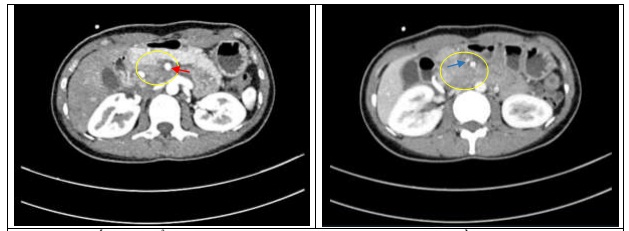

Với đặc điểm là một bệnh viện lớn nhất cả nước với rất nhiều chuyên khoa sâu, Bệnh viện Bạch Mai đã tiếp nhận và điều trị thành công cho những trường hợp như trên bằng cách phối hợp đa mô thức, trong đó nổi bật là vai trò của Khoa Phẫu thuật Tiêu hóa- Gan mật tụy, Trung tâm Y học hạt nhân và Ung bướu và Trung tâm Gây mê hồi sức. Một trường hợp điển hình là bệnh nhân nữ, 30 tuổi, được chẩn đoán ung thư đầu tụy xâm nhiễm quanh và chèn ép gây hẹp ĐM mạc treo tràng trên (Hình 1). Thông qua hội chẩn đa chuyên khoa, bệnh nhân được hóa trị tiền phẫu theo phác đồ hóa chất FOLFIRINOX tại Trung tâm Y học hạt nhân và Ung bướu và đánh giá lại sau 6 chu kỳ. Kết quả cho thấy bệnh nhân đáp ứng tốt với điều trị, thể hiện trên cắt lớp vi tính và cộng hưởng từ, khối u giảm kích thước, bớt chèn ép ĐM mạc treo tràng trên (Hình 2).

Hình 1. Kết quả chẩn đoán hình ảnh trước hóa trị: hình ảnh u đầu tụy lan rộng xung quanh (khoanh vàng), bao quanh động mạch (mũi tên đỏ) và tĩnh mạch mạc treo tràng trên, gây hẹp 90% tĩnh mạch mạc treo tràng trên (mũi tên xanh)

Hình 2. Kết quả chẩn đoán hình ảnh sau hóa trị: tổn thương thâm nhiễm vùng mỏm móc đầu tụy (Khoanh vàng) (tổn thương giảm kích thước so với phim chụp cũ không còn thấy hình ảnh thâm nhiễm quanh ĐM mạc treo tràng trên (mũi tên đỏ) hay gây hẹp TM mạc treo tràng trên (mũi tên xanh)